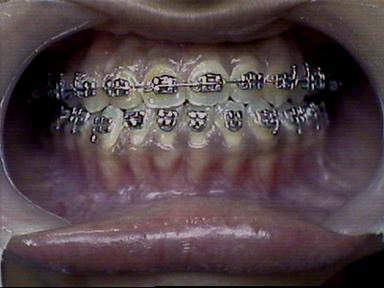

Before Treatment Intra Oral

After Treatment Intra Oral

Final Result